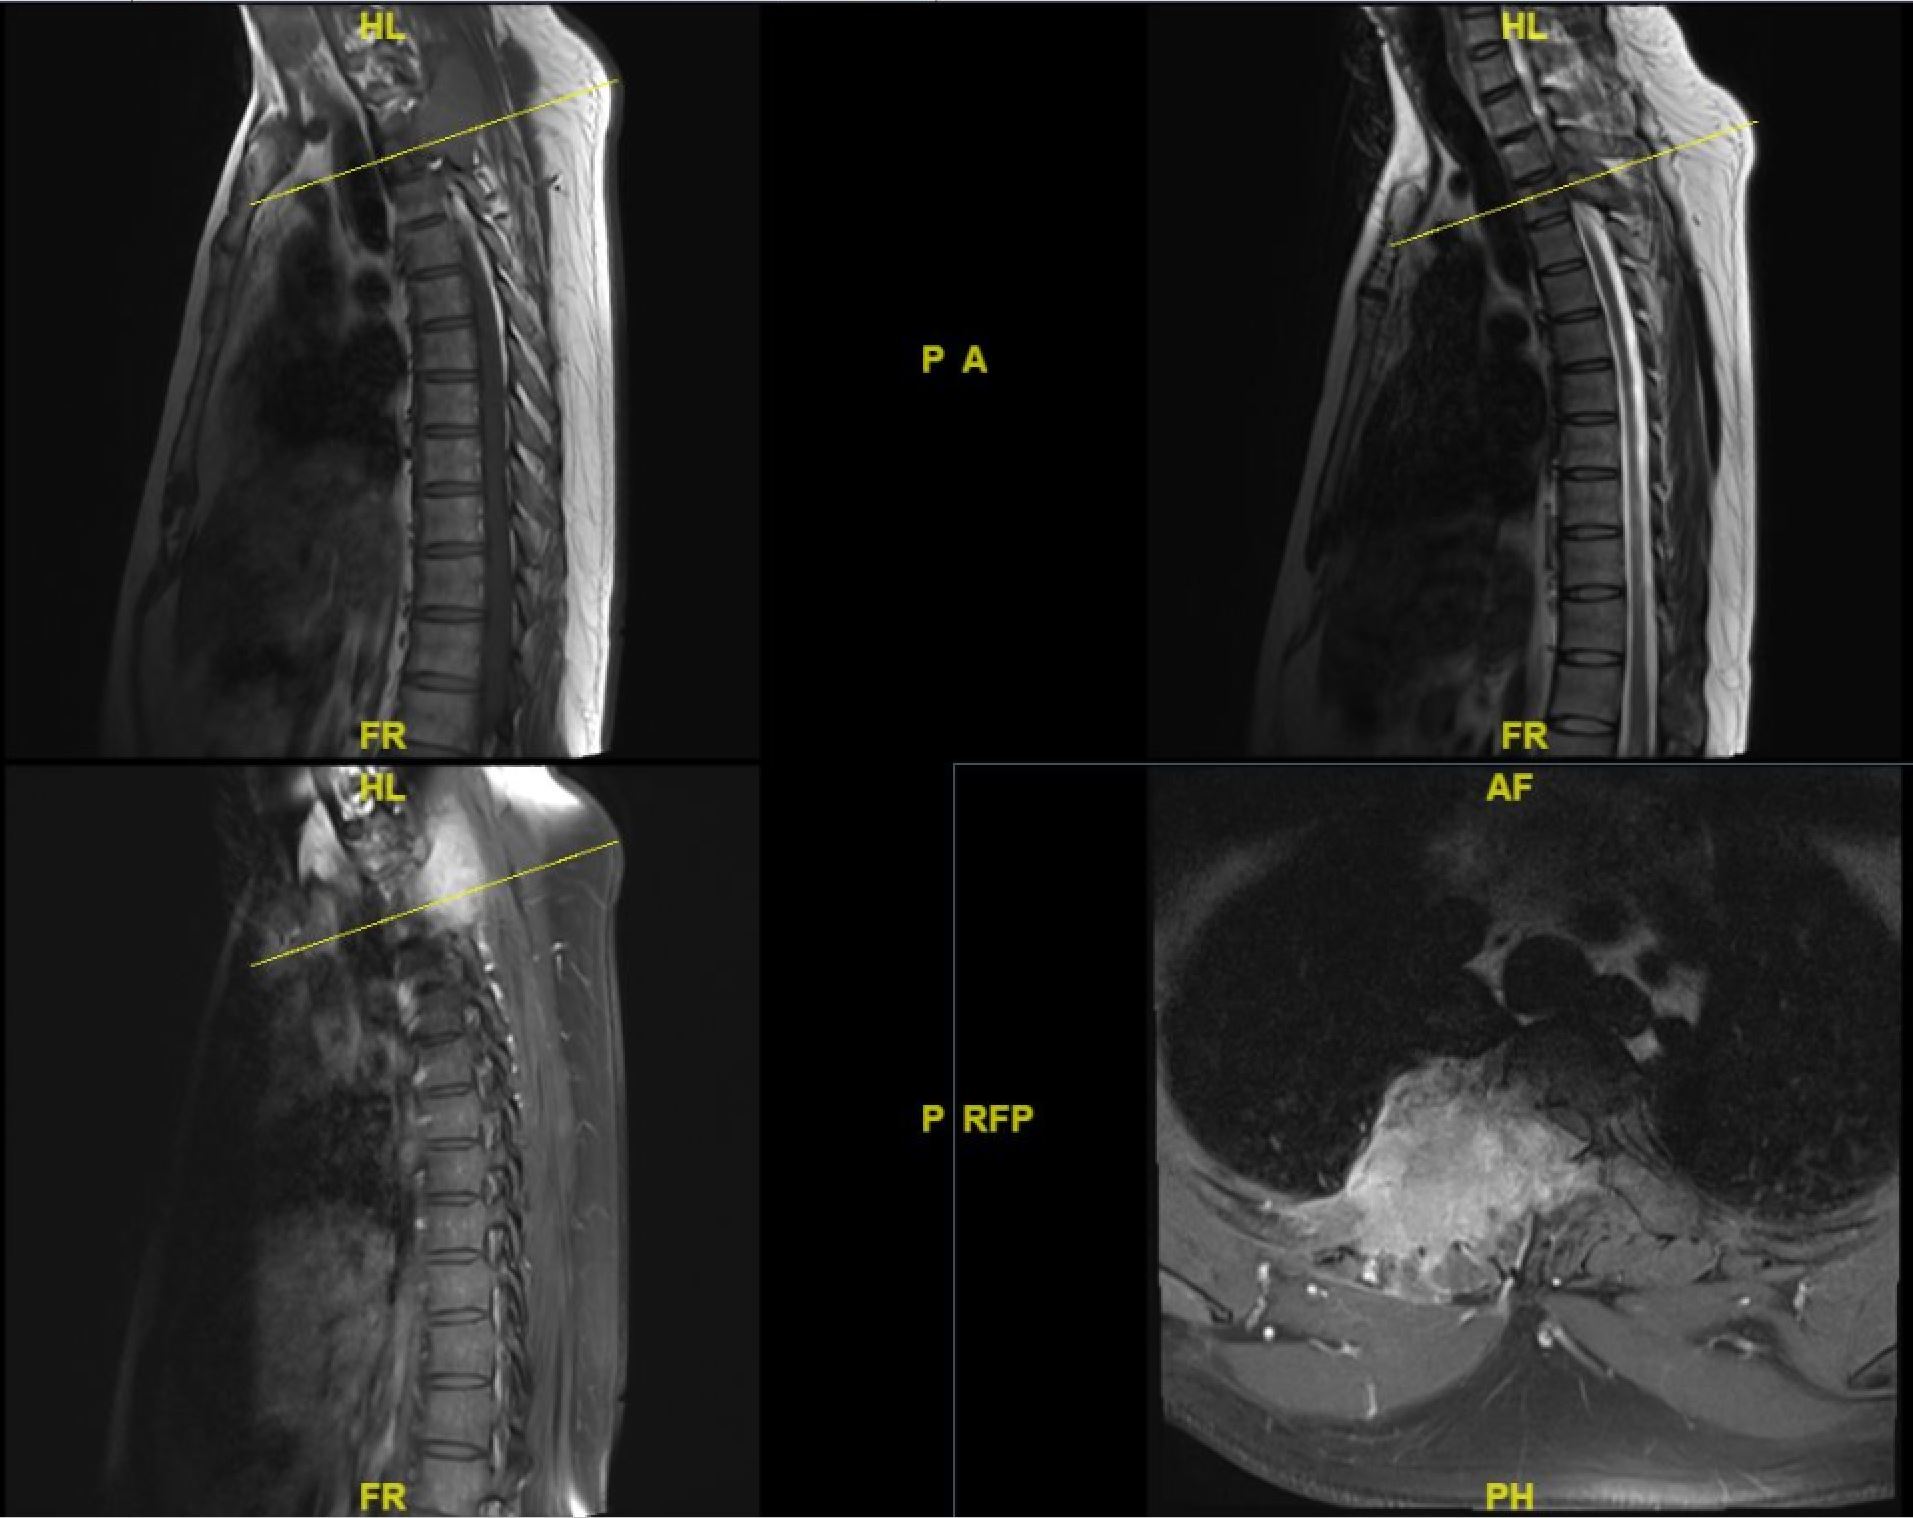

胸椎瘤

胸椎瘤,胸椎

微创切除胸椎脊膜瘤窦以河青大附院黄岛院区

巨大肿瘤近20厘米,贯穿了颈椎和胸椎.

胸椎骨巨细胞瘤手术治疗

上胸椎肿瘤穿刺活检心得体会

"病入骨髓"也能治——潍坊市中医院成功完成首例脊柱肿瘤全脊椎整块